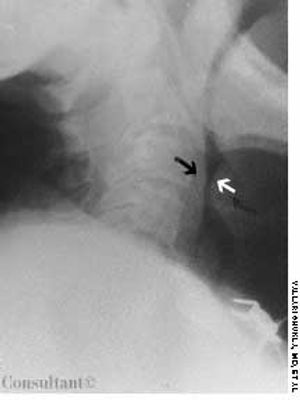

A 74-year-old nursing home resident was admitted to the hospital with shortness of breath and stridor. Radiographic examination of the neck revealed the “thumb sign” of a swollen epiglottis (Figure, white arrow); the black arrow indicates the normal posterior wall of the pharynx. Acute epiglottitis was diagnosed.